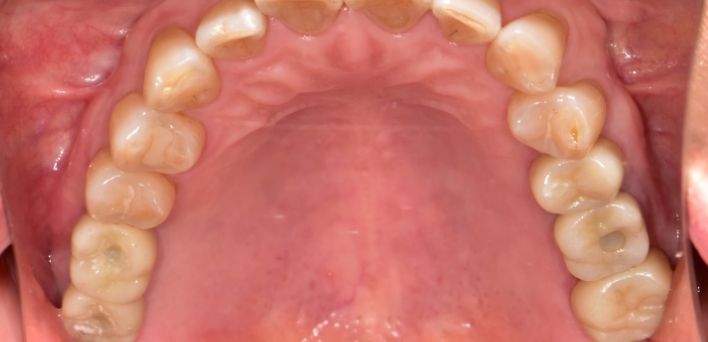

임플란트 : 손 ** 님 (50대)

Before Before

After After

2020.02.30

※ 더서울치과의원은 의료법을 준수하며 위 케이스는 실제 환자의 동의를 얻은 사례로 치료 전, 후가 동일한 환경에서 촬영되었습니다.

환자 케이스에 따라 부작용이 발생할 수 있습니다. 이 부분은 의료진의 충분한 상담과 체크를 통해 예방하고 줄일 수 있습니다.

[임플란트 부작용] 수술 후 관리가 소홀할 경우 출혈, 주위염 등의 부작용이 발생할 수 있어 구강 위생을 철저히 유지하고, 정기적인 검진을 통해 상태를 점검하는 것이 중요합니다.

환자 특징

환자 특징01무치악 상태

환자 특징02수년간 무치악으로 지내심

임플란트가 불가능할것이라

생각하고 내원

위, 아래 6개씩 식립

디지털 풀아치 임플란트